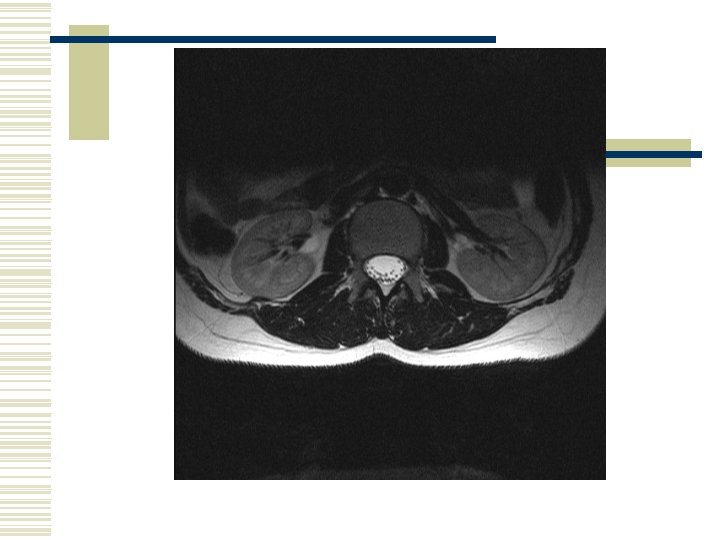

Cauda Equina Syndrome Red Flags